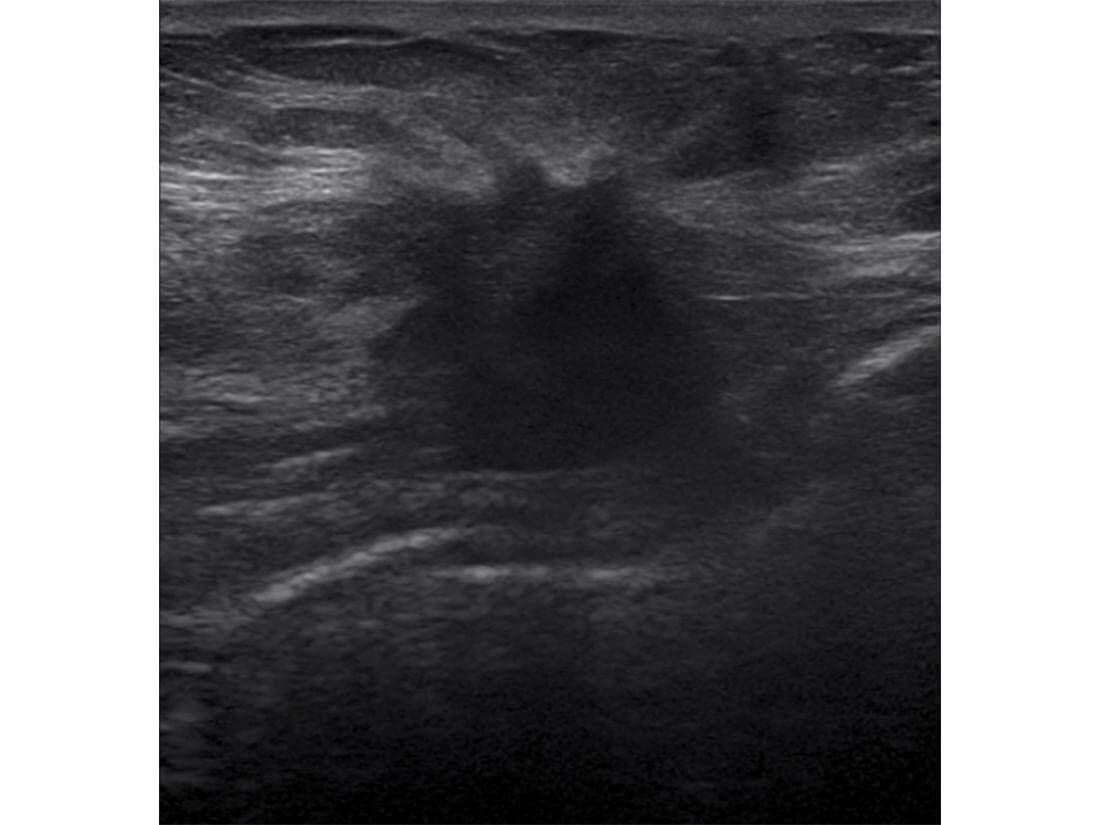

超音波検査(エコー)は、超音波を出す「プローブ」をあて、はねかえってくる超音波を画像化して、乳房内部の様子を画像にします。乳腺組織の密度が高い若年層にも向いており、マンモグラフィだけでは正確な診断がしにくい乳腺の中に埋もれたしこりを検出することができるので、マンモグラフィ検査と組み合わせることで診断率がアップします。超音波検査では、乳房に専用のジェルをつけ、その上を小さな「プローブ」をすべらせて左右の胸を調べます。

超音波診断装置「SONIMAGE HS2」は、コニカミノルタ独自のプローブ技術と画像処理技術の融合により、小さなしこりや、深い場所にあるしこりも鮮明に映し出します。